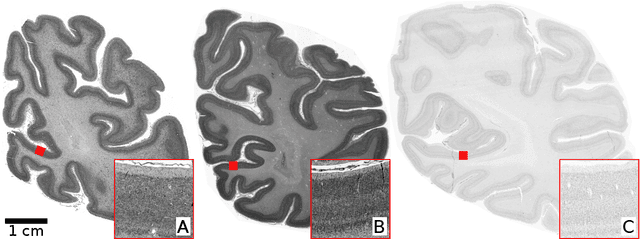

Abstract:Human brain atlases provide spatial reference systems for data characterizing brain organization at different levels, coming from different brains. Cytoarchitecture is a basic principle of the microstructural organization of the brain, as regional differences in the arrangement and composition of neuronal cells are indicators of changes in connectivity and function. Automated scanning procedures and observer-independent methods are prerequisites to reliably identify cytoarchitectonic areas, and to achieve reproducible models of brain segregation. Time becomes a key factor when moving from the analysis of single regions of interest towards high-throughput scanning of large series of whole-brain sections. Here we present a new workflow for mapping cytoarchitectonic areas in large series of cell-body stained histological sections of human postmortem brains. It is based on a Deep Convolutional Neural Network (CNN), which is trained on a pair of section images with annotations, with a large number of un-annotated sections in between. The model learns to create all missing annotations in between with high accuracy, and faster than our previous workflow based on observer-independent mapping. The new workflow does not require preceding 3D-reconstruction of sections, and is robust against histological artefacts. It processes large data sets with sizes in the order of multiple Terabytes efficiently. The workflow was integrated into a web interface, to allow access without expertise in deep learning and batch computing. Applying deep neural networks for cytoarchitectonic mapping opens new perspectives to enable high-resolution models of brain areas, introducing CNNs to identify borders of brain areas.